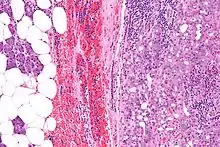

Micrograph of an acinic cell carcinoma (right of image) and acinar glands (parotid gland - left of image). H&E stain.

Basophilic, bland cells similar to acinar cells. Growth pattern: solid - acinar cells, microcytic - small cystic spaces mucinous or eosinophilic, papillary-cystic - large cystic lined by epithelium, follicular - similar to thyroid tissue.

These tumors, which resemble serous acinar cells, vary in their behavior from locally aggressive to blatantly malignant.